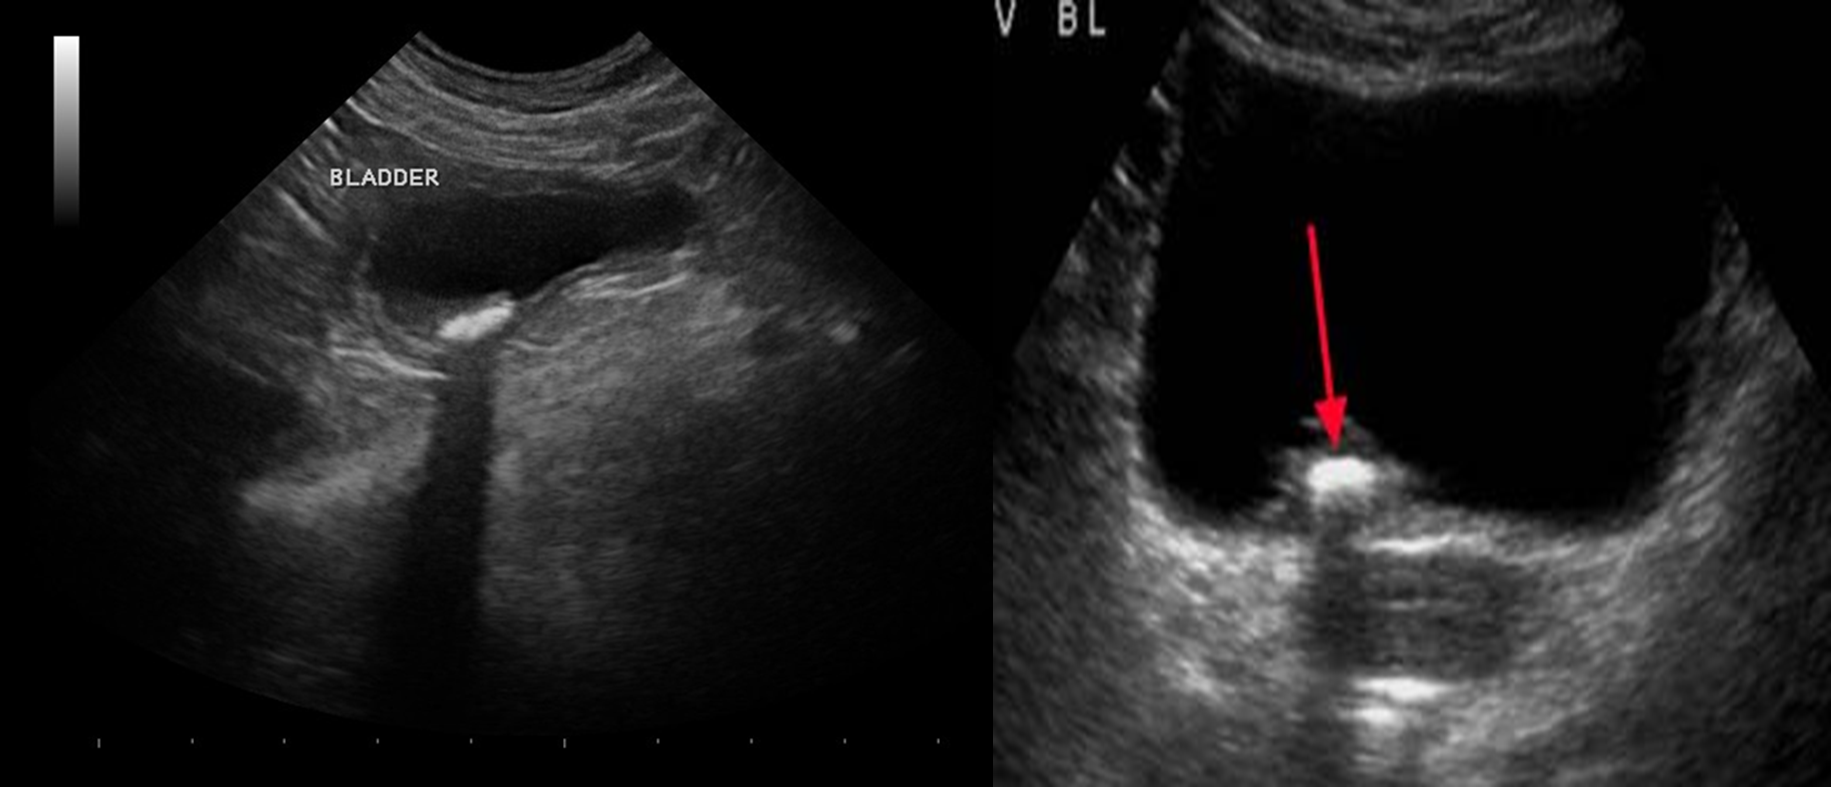

Ultrasound abdomen and pelvis

Indications:

- Suspected nephrolithiasis in patients for whom radiation exposure should be minimized (e.g., pregnant patients, pediatric patients, those with recurrent stones

Findings :

- Obstructive uropathy (e.g., hydronephrosis, hydroureter, perinephric fluid)

- Stone: hyperechoic with acoustic shadowing

(1st img) There is a round, hyperechoic lesion at the upper pole of the kidney in the renal parenchyma, which shows a dorsal acoustic shadow and is most likely a kidney stone. The central areas of the kidney show, as far as can be seen in this image, no dilation, which indicates no obstruction.

Bladder calculus